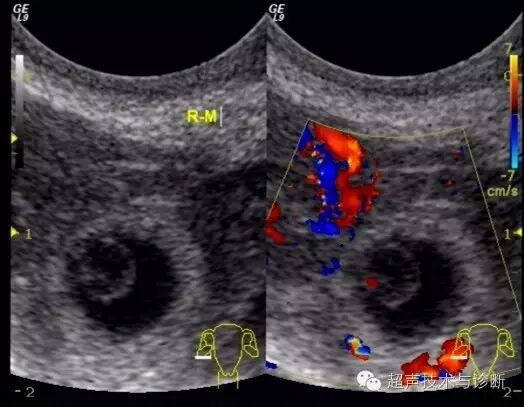

4、超声检查如下(2016。02。01):子宫形态大小正常,宫腔内见一不规则囊性结构,大小4x2cm,透声差,未见双环征及胚芽结构,CDfi未见血流。双侧卵巢可见,右侧附件区可见一囊性结构,大小3x2cm,其内可见胚芽及心管博动。

入院血HCG及超声检查图像如下;